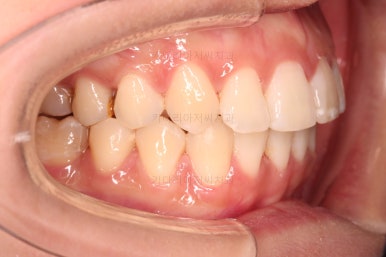

어느새 틈도 다 닫히고요.

마무리 과정만 남았습니다.

틈이 다 없어졌고, 교합도 양호합니다.

무엇보다 임플란트 없이 결손부위가 깔끔하게 채워졌고요.

매우 다행으로 사랑니도 다 있었기 때문에 마치 큰 어금니가 다 있는 것과 같은 상황이 되었습니다.

역설적이게도 손상된 큰 어금니가 없었던 부위는 작은 어금니를 발치함으로 인해 오히려 치아 갯수가 모자라 보이는 상황까지 왔네요.(어금니가 결손된 부분이 더 자연스럽게 보이는 상황)